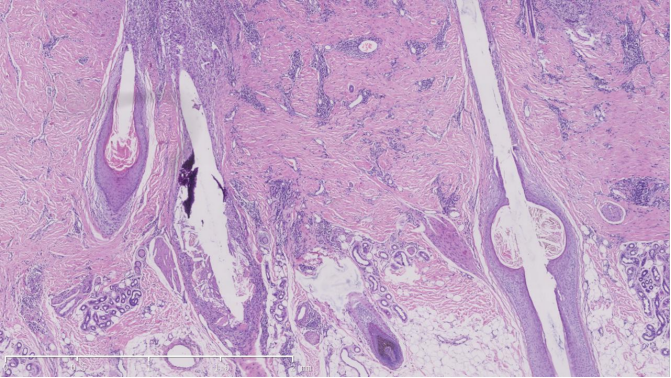

病理特征

组织病理显示,核心病变以毛囊峡部为中心,可见毛囊结构变形、中央角栓形成及外毛根鞘向内毛根鞘凸起。炎症浸润攻击峡部及以上毛囊区域,导致上皮破坏及周围淋巴细胞、组织细胞浸润与纤维化。毛囊间真皮内胶原广泛瘢痕化改变伴有血管周围淋巴/